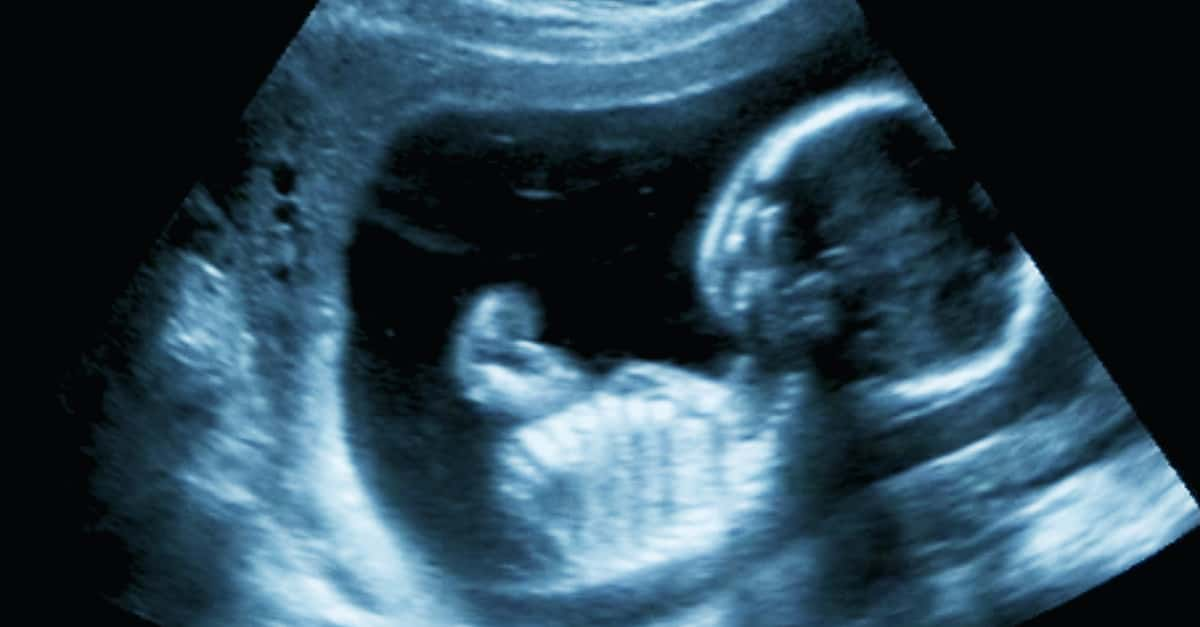

In the Womb

Genetics are complicated, tricky, and still mysterious even in the 20th century. Because our DNA works overtime to make us who we are, it takes a few shortcuts where it can, including when we are just embryos inside our mothers’ wombs. As we grow from fetuses to full-on babies, our genes map both male and female babies off of a handy “blueprint.”

In other words, up to a certain point, male and female embryos are the same. During the early weeks of pregnancy, both male and female babies develop a few identical key characteristics—including, as you might have guessed, nipples. It’s only after about six or seven weeks that the differently sexed bodies start to diverge: in particular, the male baby starts developing testes and, accordingly, testosterone.

Suddenly, less than two months into a male baby’s existence, it has nipples—and no real need for them. Which leads to yet another question: Why keep male nipples around?